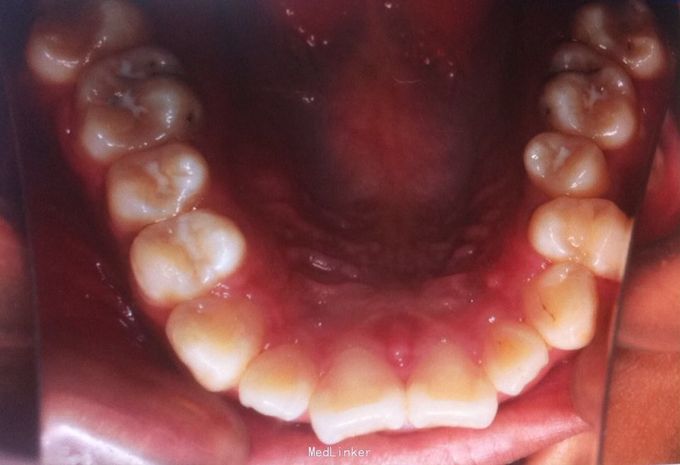

恒牙期 左侧磨牙中性关系,右侧远中关系 前牙三度深覆合 上合牙列中度拥挤,下颌重度拥挤 下颌中线偏右 关节有弹响

安氏二类,牙列拥挤 拔牙矫治,拔除14、24、34、44,强支抗,排齐整平上下牙列,矫治后磨牙中性关系,前牙覆合覆盖正常,面型略改善